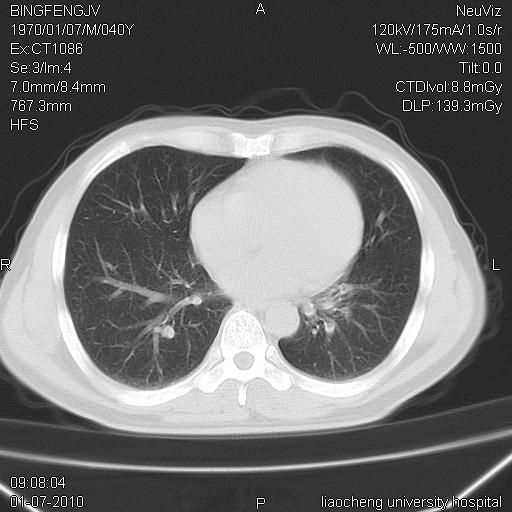

标题: CT23764B:男 40 肺部CT [打印本页]

标题: CT23764B:男 40 肺部CT

治疗2周后

炎症性病灶,继发性改变。

考虑左肺上叶近胸膜下炎症并肺气囊形成。

炎症,大部吸收。